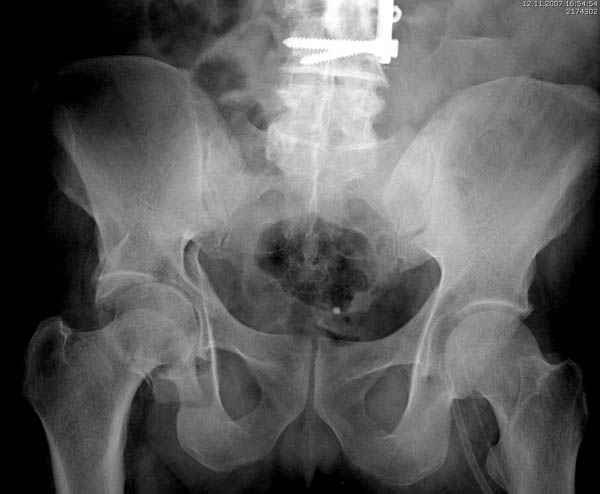

По возможности вышлите снимки, сканы таза до

реконструкции, интраоперационные.

По снимку создается впечатление о высоком поперечном переломе, задней колонны, стенки; почему не пользовались *magic screw*?

Снимки здесь....